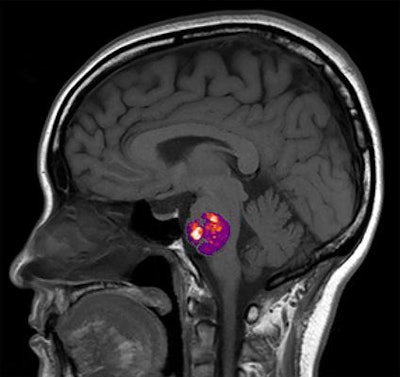

A team led by Dr. Sean Polster of the University of Chicago used genomic analysis techniques to compare stool samples from 122 patients who had at least one cavernous angioma seen on brain MRI to patients who did not have any angiomas.

The study is the first to show in humans that a "permissive microbiome" is associated with the formation of neurovascular lesions in the brain, and it supports increasing evidence of the role of gut bacteria in brain health, according to Polster and colleagues.